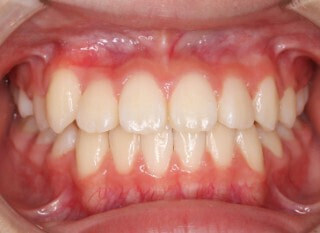

治療前

終了時